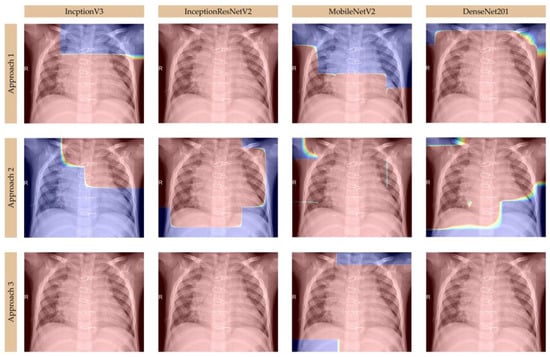

Moreover, we analyzed Grad-CAM visualizations for deep learning models—InceptionV3, InceptionResNetV2, MobileNetV2, and DenseNet201—in classifying healthy lungs, viral pneumonia, and bacterial pneumonia from chest X-ray images, using multiple Grad-CAM approaches to highlight key decision-making areas, as presented in Figure 4, Figure 5, and Figure 6, respectively. In healthy cases, models like InceptionV3 and DenseNet201 show minimal activation, primarily along the ribcage or lung periphery, while viral pneumonia is characterized by diffuse, bilateral activation across both lungs, often including the heart region [,], as seen in MobileNetV2 and DenseNet201, which effectively capture interstitial changes. Bacterial pneumonia, in contrast, is identified by sharp, localized activation, typically within one lung lobe [], with DenseNet201 excelling in its detection due to its highly focused heatmaps, while InceptionResNetV2 also well differentiates the sharply defined activations in specific lobes. Grad-CAM approaches, particularly Approach 3, provide the clearest visualizations, revealing sharp, focused bacterial pneumonia regions and broader, generalized viral patterns, while Approach 1 highlights initial lung field activations, and Approach 2 refines distinctions between pneumonia types. MobileNetV2 performs best for viral pneumonia due to its strong central lung and heart activation, DenseNet201 is the most accurate for bacterial pneumonia, with its distinct lobar focus, and InceptionResNetV2 offers a balanced performance for both. Key takeaways include minimal activation in healthy cases, diffuse patterns in viral pneumonia, and localized, sharp activations in bacterial pneumonia, with DenseNet201 emerging as the most precise model for distinguishing between the two pneumonia types [,]. Overall, Grad-CAM effectively illustrates how these models interpret pneumonia patterns, confirming DenseNet201’s superiority for bacterial pneumonia and MobileNetV2’s strength in viral pneumonia detection.

Figure 6.

Grad-CAM visualizations for bacterial pneumonia.